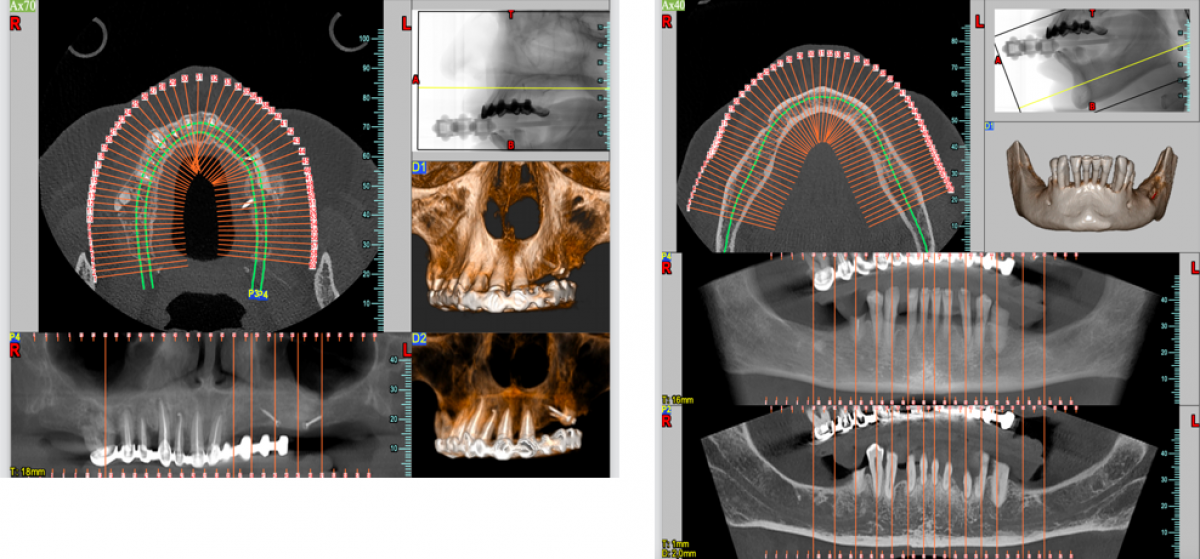

A female patient aged 16, in a good state of systemic health, comes to my attention complaining about food impact and difficulty in using dental floss in ​​the upper left sextant. On physical examination, a significant accumulation of plaque is seen at the interproximal level. The radiographic examination performed by bitewing revealed a carious lesion of type D3 of tooth 2.5 according to the classification of Marthaler and Lutz. (Fig 1)